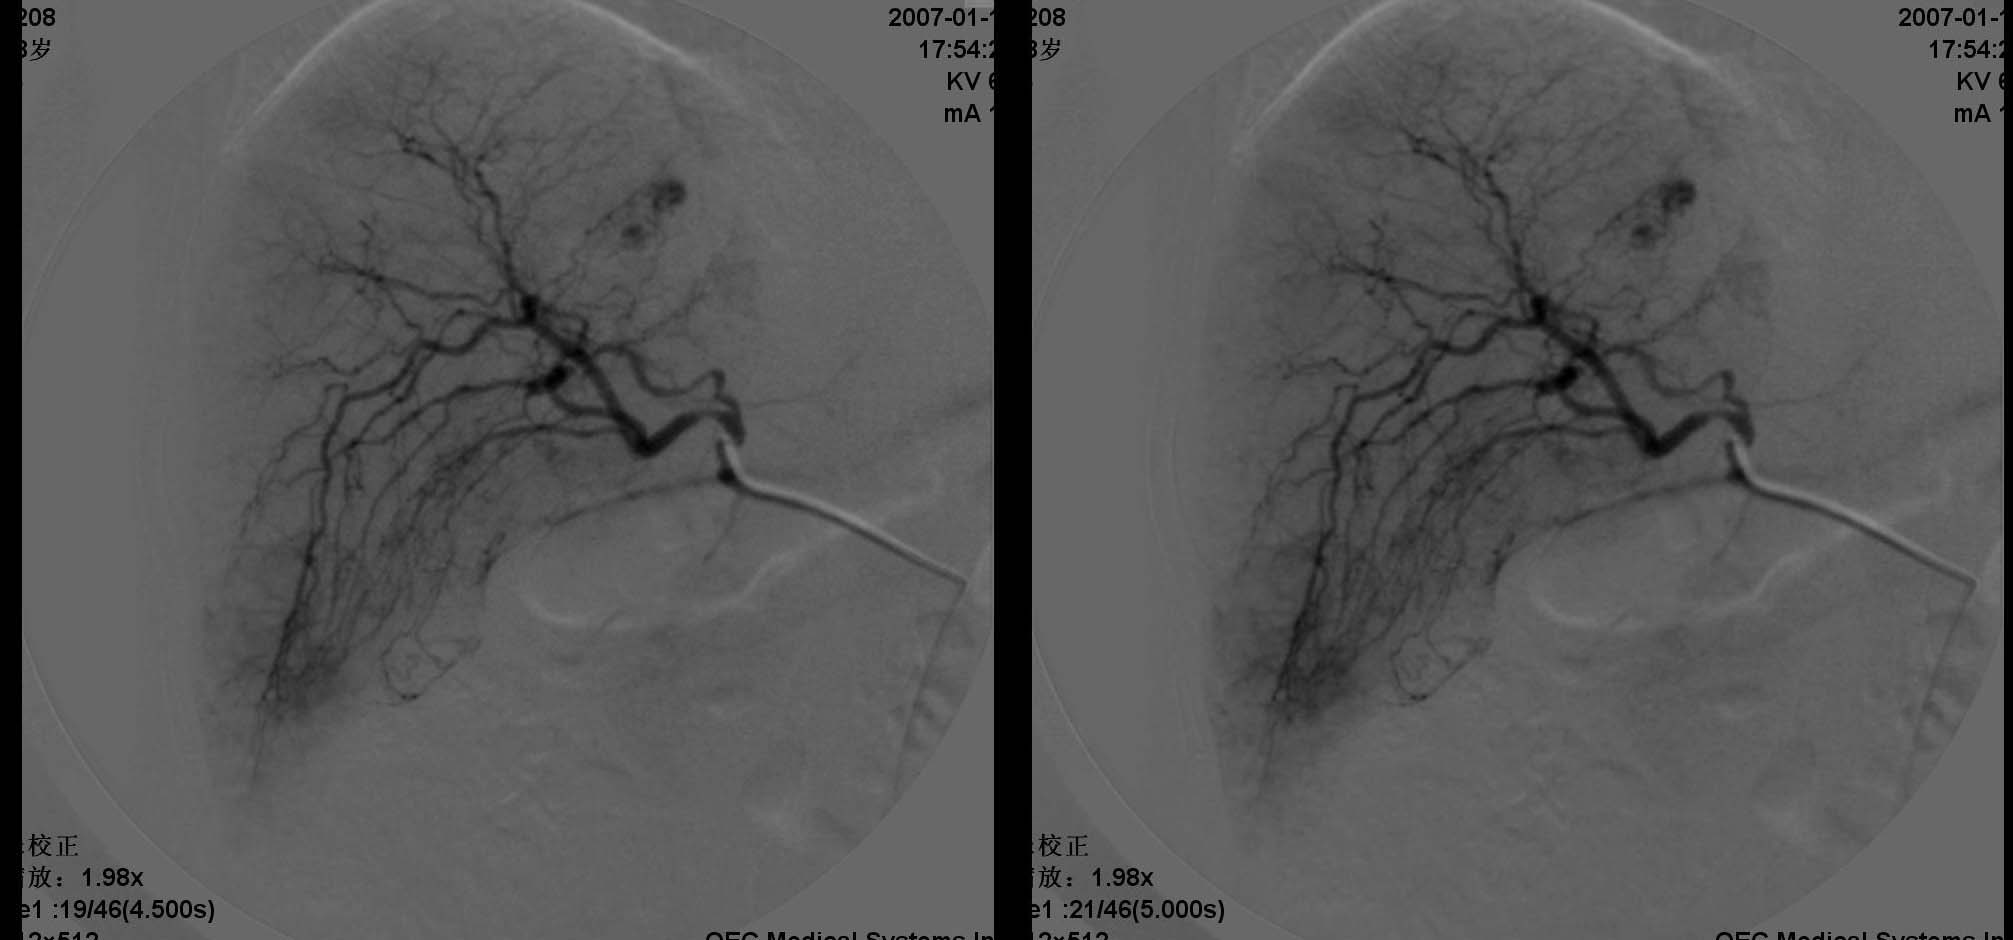

动脉期见肝右动脉稍增粗,实质期肝右叶可见两个类圆形染色区,以边缘部为著.脾脏病灶类似.首先考虑转移瘤.

肝转移瘤的表现多种多样,血供丰富的肝转移瘤常呈现与肝细胞癌相似的表现,肝动脉增粗、扭曲,分支血管增多、紊乱呈网状,血管僵硬、受压移位等.巨块型转移灶实质期肿瘤染色还可见到较明显的中心性坏死所显示的中央低密度区。少血供者,肿瘤血管常较稀少、纤细、僵直或包绕,实质期肿瘤染色淡薄或不显影,而在肝实质染色衬托下形成低密度充盈缺损区。中血供之表现介于上述两者之间。在门静脉期,无论是多、中、少血供肝转移瘤,均显示与转移灶在动脉晚期和实质期类似的肿瘤染色。